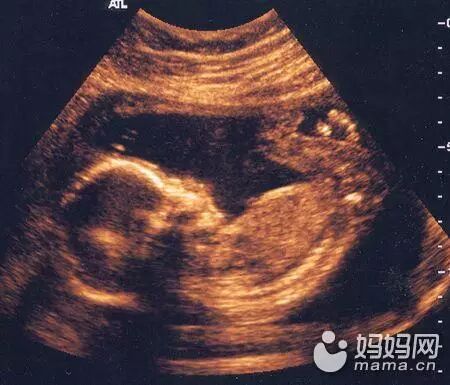

男婴在子宫里勃起,女婴也会自慰

大多数妈妈不喜欢思考她们的男婴是否会勃起,即使她们是很开放的年轻人,但事实是许多男婴当他们还在子宫里的时候就开始犯错了。上面的这幅图片是唯一被超声波图像抓拍到的男婴勃起图片,而且还不仅是男孩,女孩也会有类似自慰的情况。只不过只有男孩的勃起可以被超声波照到罢了。如果在怀孕期间有性生活似乎有点令人毛骨悚然,想想你的孩子正在做一些当你在做爱时大脑中所想的事情吧。